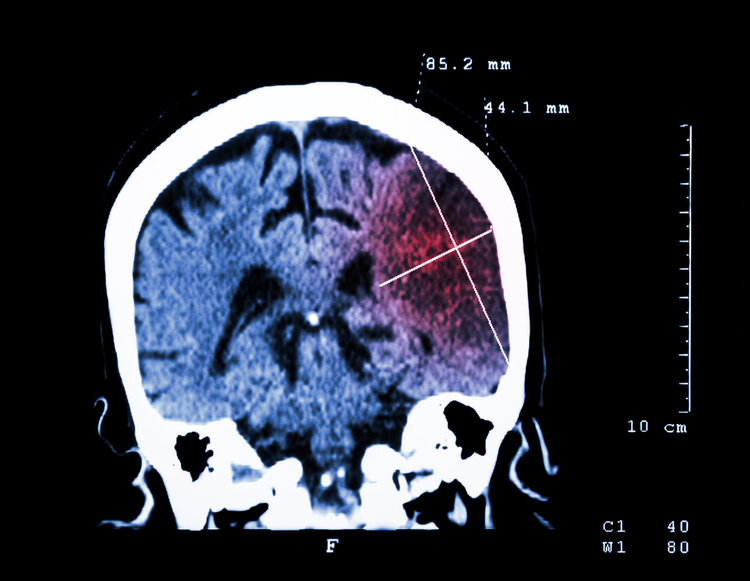

脑梗发生在逐渐趋于年轻化,大吃大喝中要小心疾病悄悄积累。有不良饮食习惯的人,建议最好每年定期做脑CT体检,看看脑部血管是否存在病变,积极预防脑梗。